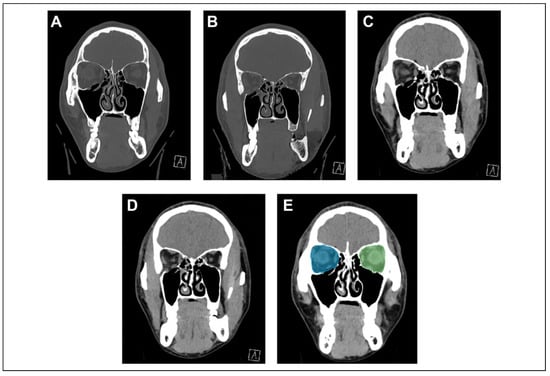

Intact Periorbita Can Prevent Post-Traumatic Enophthalmos Following a Large Orbital Blow-Out Fracture

Clinical Report